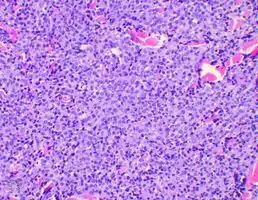

Bone marrow biopsies are performed to ensure the disease is localised; and in SPB or extramedullary plasmacytoma there will not be an increase of monoclonal plasma cells. Tissue biopsies of SPB and extramedullary plasmacytoma are used to assess the phenotype of the plasma cells. Histological analyses can be performed on these biopsies to see what cluster of differentiation (CD) markers are present and to assess monoclonality of the cells. CD markers can aid in the distinction of extramedullary plasmacytoma from lymphomas.[5][9]

Plasmacytoma is a tumor of plasma cells. The cells are identical to those seen in multiple myeloma, but they form discrete masses of cells in the skeleton (solitary plasmacytoma of bone; SPB) or in soft tissues (extramedullary plasmacytoma; EP). They do not present with systemic disease, which would classify them as another systemic plasma cell disorder.[10]